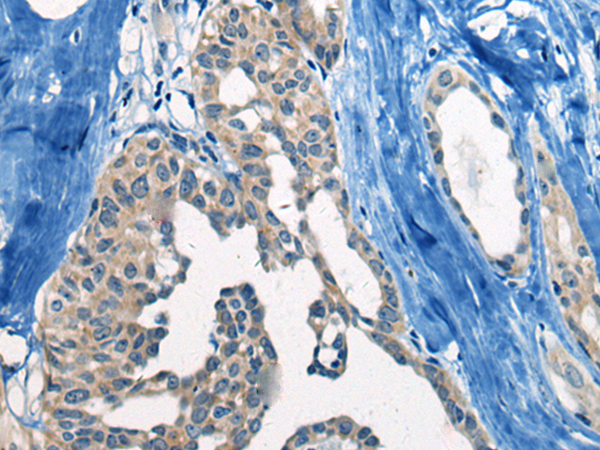

ELISA, IHC |

IHC positive control: |

Human liver cancer and Human thyroid cancer |

IHC Recommend dilution: |

20-100 |